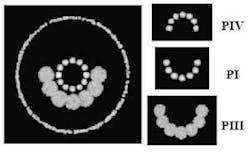

Pablo Artal and Juan Tabernero at the University of Murcia (Murcia, Spain) have built a prototype imaging system for recording reflections (called Purkinje images) from four ocular interfaces-air-cornea (PI), cornea-aqueous (PII), aqueous-lens (PIII), and lens-vitreous (PIV)-in vivo. The prototype imaging system contains a chin and forehead rest for the subject; a semicircular array of infrared LEDs to illuminate the eye; a telecentric camera objective and CCD camera to collect and record the reflections; an array of LEDs for the subject to fixate on; and other optical components.

When an illumination source is aligned with principle line of sight in a well-aligned human eye, the reflection images align around a common center. PI and PII usually overlap due to small corneal thickness. PIII appears largest, and PIV appears inverted. The outermost circle, in the large image on the left of well-aligned reflections, traces the circumference of the pupil. The relative positioning of the Purkinje images changes, however, with misalignments, either among ocular surfaces or between the illumination source and the line of sight. The new instrument is expected to prove useful in basic studies of the eye and in clinical ophthalmology. Contact Pablo Artal at [email protected].